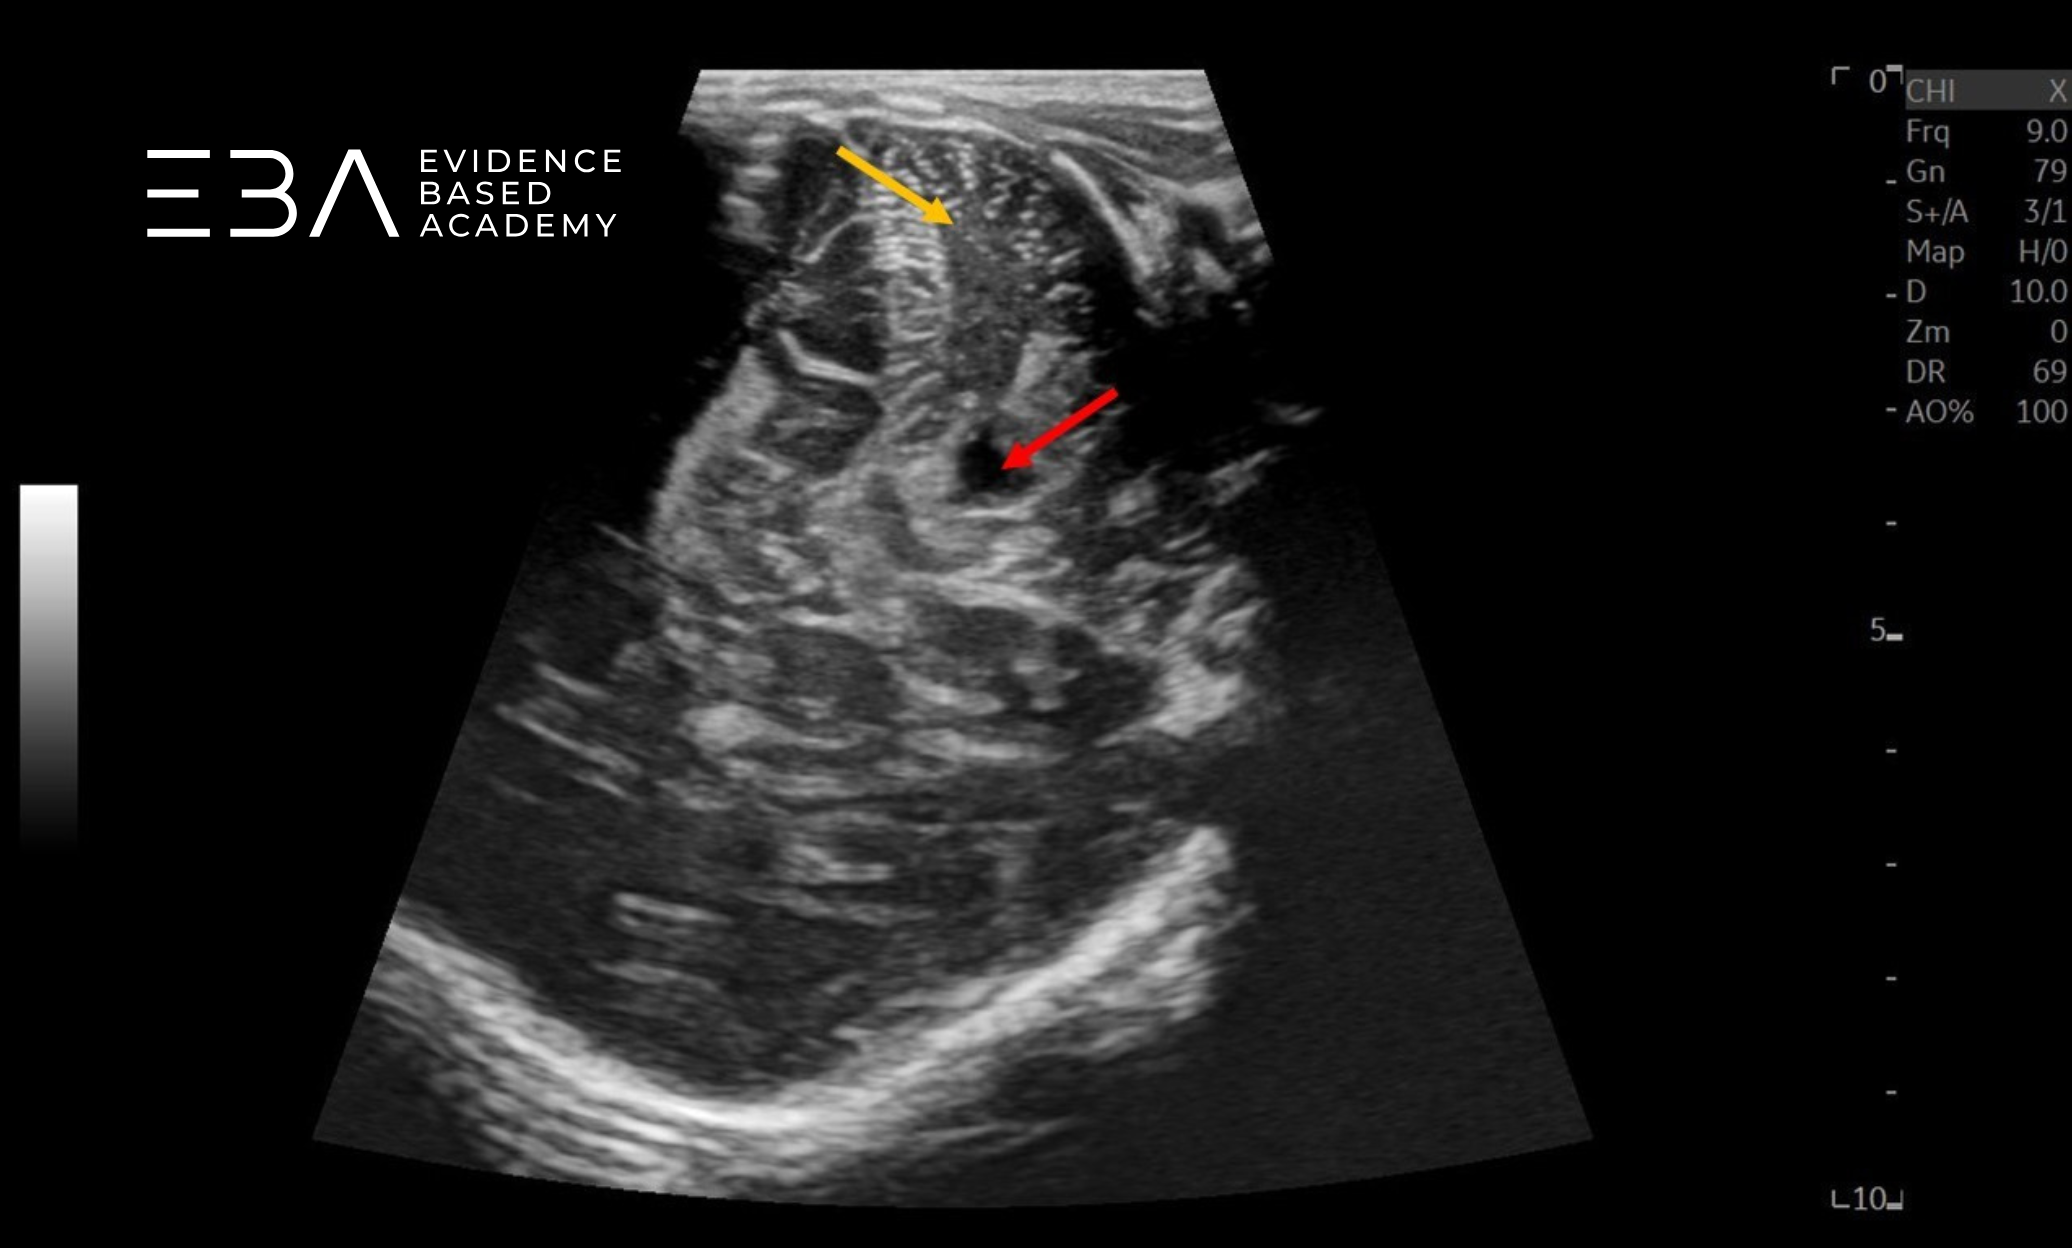

Badanie przez ciemiączko sutkowe

Obrazowanie przez ciemiączko sutkowe pozwala ocenić blaszki móżdżku, zbiornik wielki i komorę czwartą pod kątem prawidłowego wyglądu i wymiarów (6). Widoczne są również niektóre struktury nadnamiotowe, w tym tylna część układu komorowego, niekiedy komora trzecia, a także wzgórze, konary mózgu i zbiorniki podstawy mózgu (2). U wcześniaków przez to okno możemy dobrze uwidocznić również przeciwległą półkulę móżdżku (3).

zdj. 22

Głowica liniowa – badanie przez ciemiączko tylno-boczne. Półkula móżdżku (żółta strzałka), komora czwarta (czerwona strzałka).